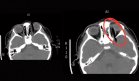

El 14 de marzo de 2018, el paciente reingresó con un cuadro clínico de 10 horas de evolución, caracterizado por disminución de la agudeza visual bilateral, visión borrosa transitoria, cefalea frontal y parietal punzante, y caída desde su propia altura debido a alteración visual. En el examen físico se encontraba alerta, con visión bilateral de 20/20, fondo de ojo normal y sin signos de focalización neurológica. La tomografía de coherencia óptica fue normal y los cuatro miembros presentaban fuerza 5/5.

El estudio del líquido cefalorraquídeo (LCR) descartó encefalitis, sin pleocitosis ni alteraciones en el ácido láctico. Se identificaron autoanticuerpos anti-AQP4 en LCR (4,53 U/mL, con punto de corte <3 U/mL) y tres bandas oligoclonales tipo 2. La RM cerebral y de nervios ópticos, siguiendo protocolo de enfermedad desmielinizante, fue normal.